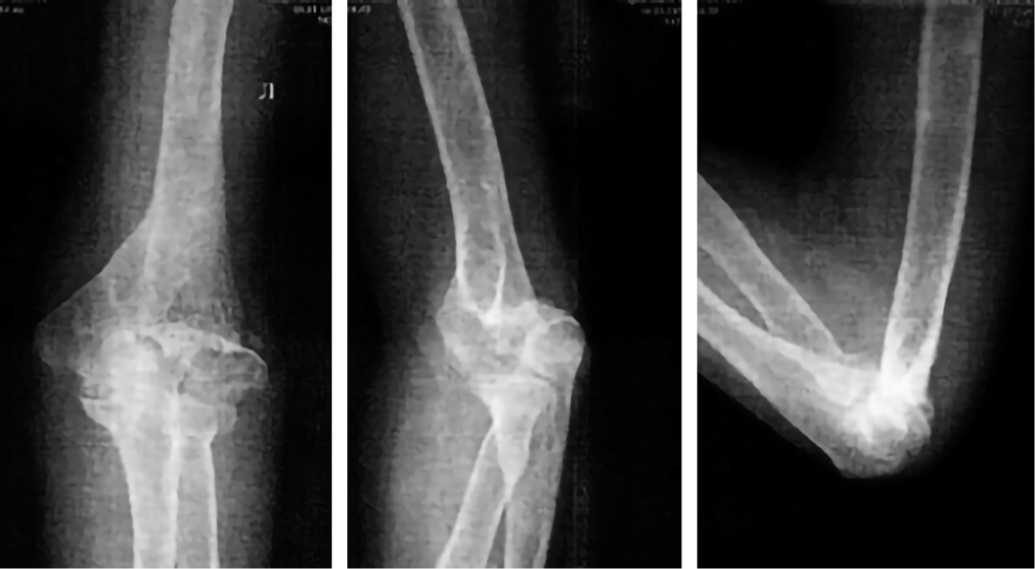

На следующий день после выполнения операции сделана контрольная рентгенография левой плечевой кости в 2-х проекциях, ЛФК для локтевого сустава и мышц проводилась с первого дня после операции с применением описанных выше методов. На контрольных рентгенограммах, сделанных через 2 года после операции, видны признаки консолидации перелома нижней трети левой плечевой кости, металлоконструкции были удалены (рис. 6). Отмечается полный объем движений в локтевом суставе (рис. 7).

Рис. 6. Рентгенограммы после удаления металлоконструкций

Fig. 6. Radiographs after removal of metal structures